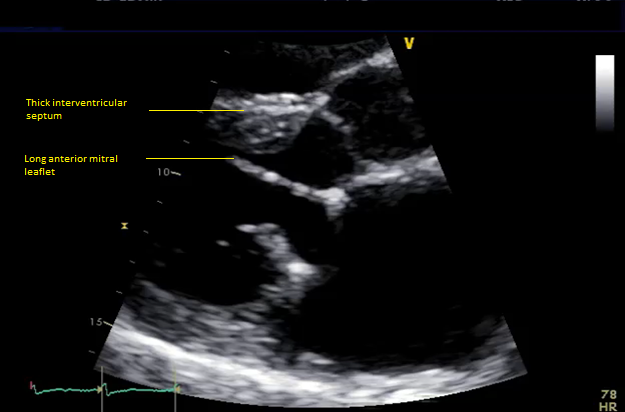

Six months later, the patient had continued shortness of breath and a transesophageal echocardiogram revealed severe mitral regurgitation with evidence of mild peri-prosthesis leak (video 2). Due to his elevated surgical risk (STS score of 9%),patient underwent a valve-in-ring (ViR) transcatheter mitral valve replacement (TMVR) with a 29mm Edwards Sapien3 via a trans-septal approach (using 14mm balloon for septostomy). Pre-procedure planning was done based on transthoracic & transesophageal echocardiography and multi-detector CT (without measurement of neo-LVOT with a simulated valve) showing long anterior leaflet (27mm), thick interventricular septum (1.5cm), LVOT diameter (1.8cm), aorto-mitral angle of 64 degrees (Figure 1, video 1). Immediately post TMVR, patient did well with stable hemodynamic but over next 2-3 days systemic pressures started to drop along with decline in renal function was noted. Trans-thoracic echocardiogram showed systolic anterior motion (SAM) of the anterior mitral leaflet with elevated LVOT gradient of 88mmHg (baseline LVOT gradient of zero mmHg prior to TMVR). Furthermore, there was evidence of a continued iatrogenic atrial septal defect with continuous left to right shunt. Percutaneous left ventricular assist device (Impella CP) was placed for hemodynamic support for 24 hours with improvement in renal function. The patient underwent alcohol septal ablation of 1st large septal perforator (injected 1.5ml of pure alcohol) with drop of LVOT gradient from 80 mmHg to 20mmHg. Next further septal ablation was performed by injecting another 1 ml of pure alcohol into the basilar branch of 2nd septal perforator with final LVOT gradient of 10mmHg (video 3).The patient was able to be discharged and his renal function recovered, however, he still continued to have NYHA functional class III symptoms.

Figure 1 Pre-mitral valve replacement multi-detector CT scan showing thick interventricular septum and aorto-mitral angle (panel A), and transesophageal echocardiogram showing long anterior mitral leaflet and left ventricular outflow tract diameter.